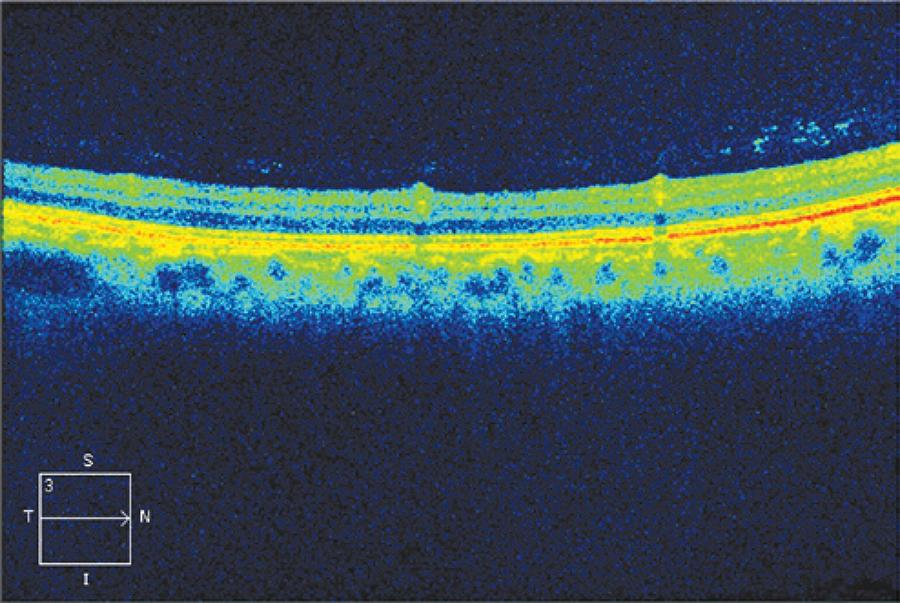

Figure 3 Optical coherence tomography (OCT) of the region, showing perivascular inflammation, with local vitreitis.

Pale yellowish dots were mainly overlying vasculature and also in periphery. OCT was performed and indicated location in the vi-treous-retina transition.

Fundus photographs showed that these dots were overlying vasculature and also located at the periphery. OCT revealed that they were located in the vitreous-retina transition (Figure 3), probably due to local perivasculitis, which is typical in treponema infection, as the local vitreitis also suggests. After treatment, ocular findings disappeared in all patients but one, a 55-year-old, female without HIV infection; even with resolution of ocular symptoms, the findings remained present 4 months after treatment with crystalline penicillin.